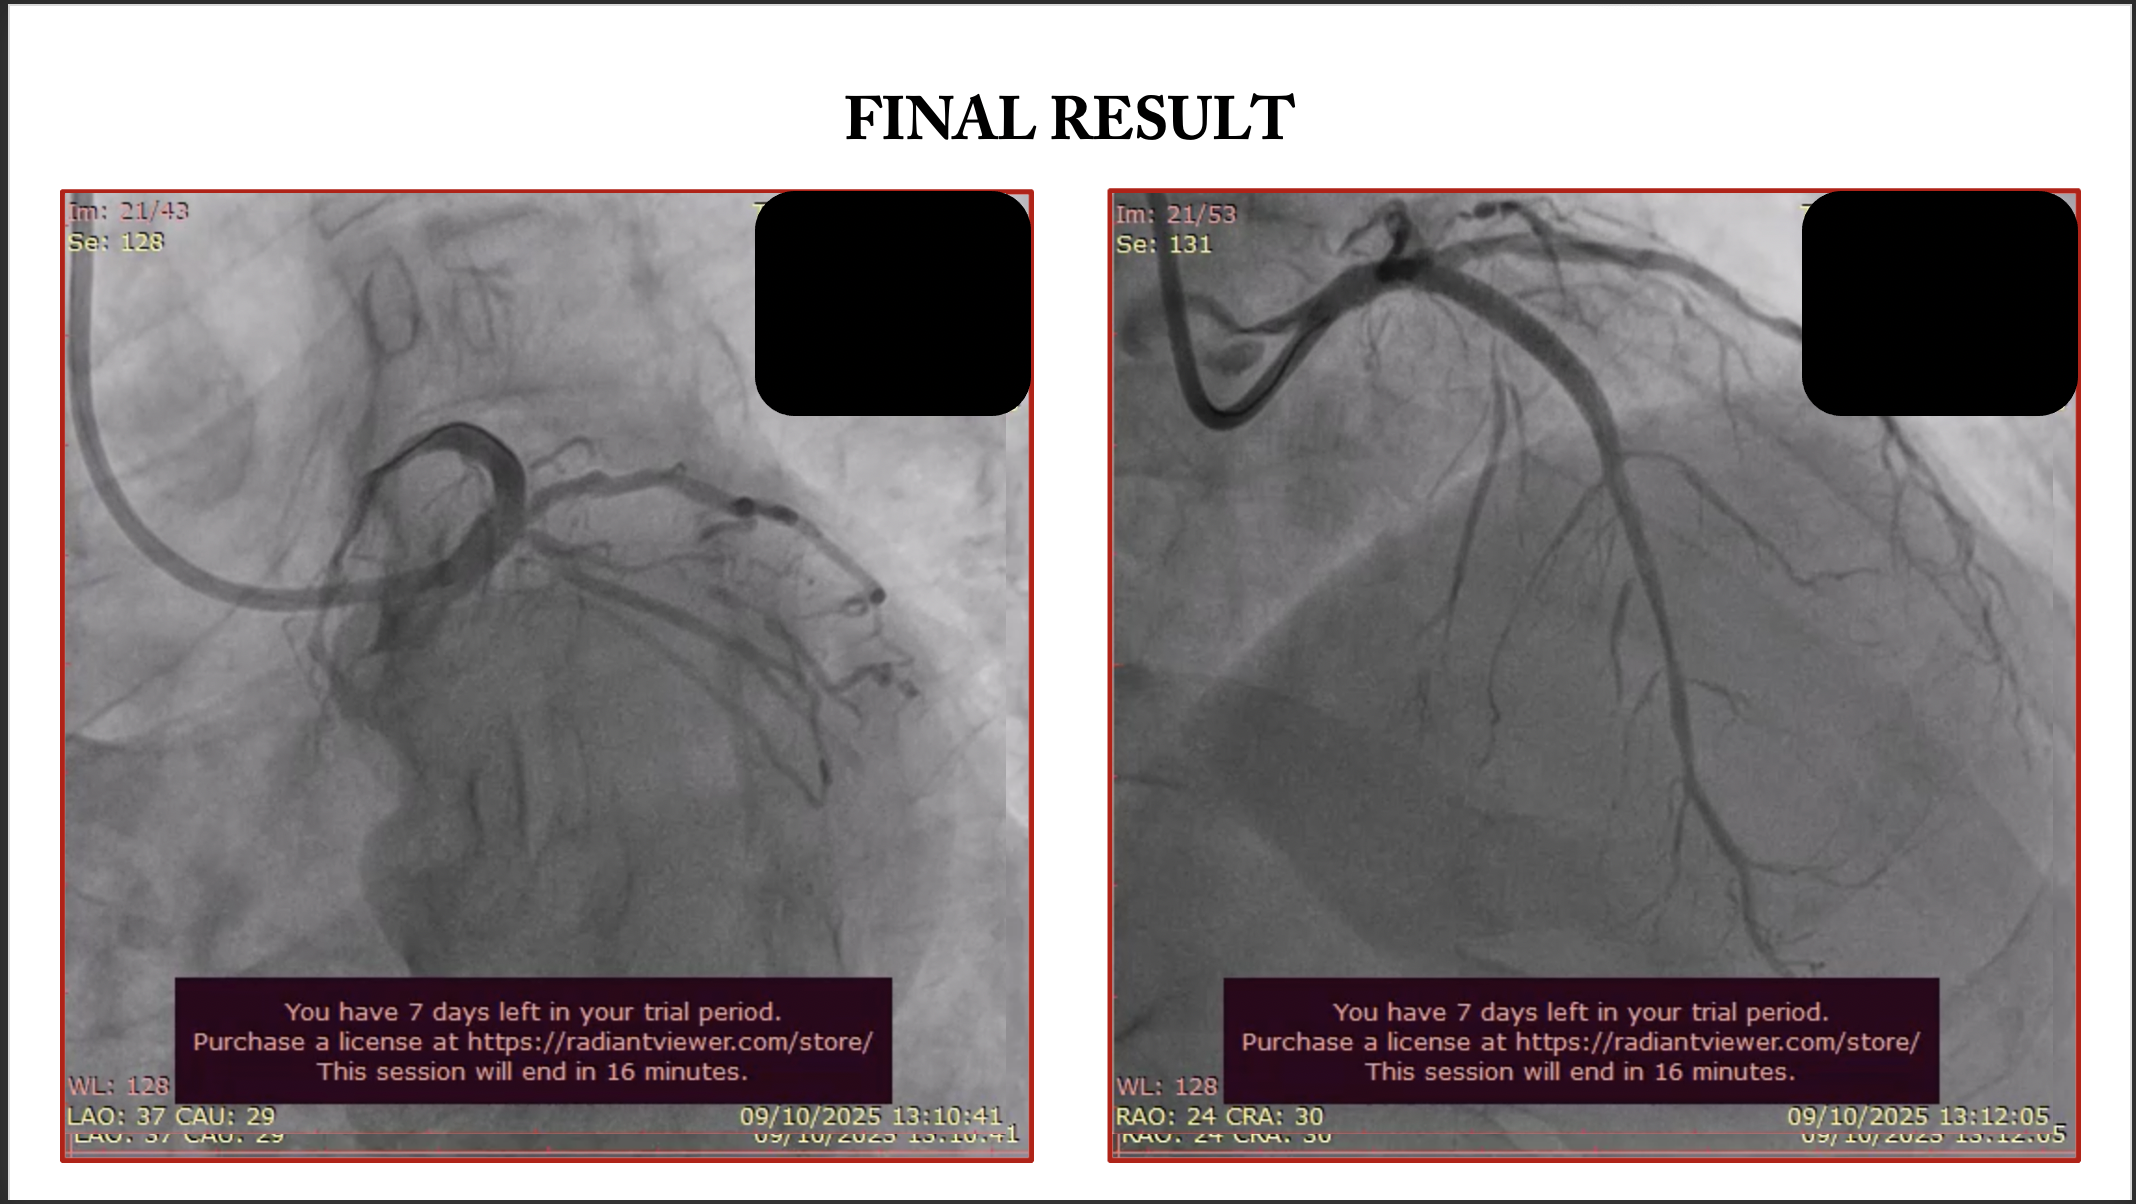

An 7 Fr EBU 3.5 guiding catheter was engaged into the left coronary artery via the right radial artery. A SION guide wire was initially inserted into the LAD. To protect the two large side branches, a BMW guide wire and a runthrough with a Finecross microcatheter were introduced into the intermediate branch and LCX, respectively. According to the angiographic and intravascular ultrasound images, we decided to perform direct crossover stenting from the LMT to LAD using the simultaneous jailed balloon and jailed microcatheter technique. After lesions preparation, Ramus intermediete treated with 1 DEB 2.5x25 mm. A DES 3.5x38 was advanced into the LAD, and a semicompliant balloon 2.0 ¡¿ 15 mm was advanced into the intermediate branch. Subsequently, a Finecross microcatheter was introduced into the LCX. The simultaneous jailed balloon and jailed Finecross technique was then performed. The side branch balloon in the intermediate branch was initially inflated at nominal pressure (12 atm). The main branch stent balloon in the LMT to LAD was then inflated at nominal pressure (11 atm), which simultaneously jailed the side branch semi-inflated balloon in the intermediate branch and the Finecross microcatheter in the LCX. Blood flow was preserved in both the intermediate branch and the LCX after main vessel stenting, and there were no signs of plaque or carina shift into the side branches. Distal LAD was treated with hybrid approach 1 DCB 2.5x35 mm.

The simultaneous jailed balloon and jailed microcatheter technique is a novel and effective double side branch protection technique for the treatment of left main trifurcation disease in selected patients. Further studies on this technique in larger populations are needed.